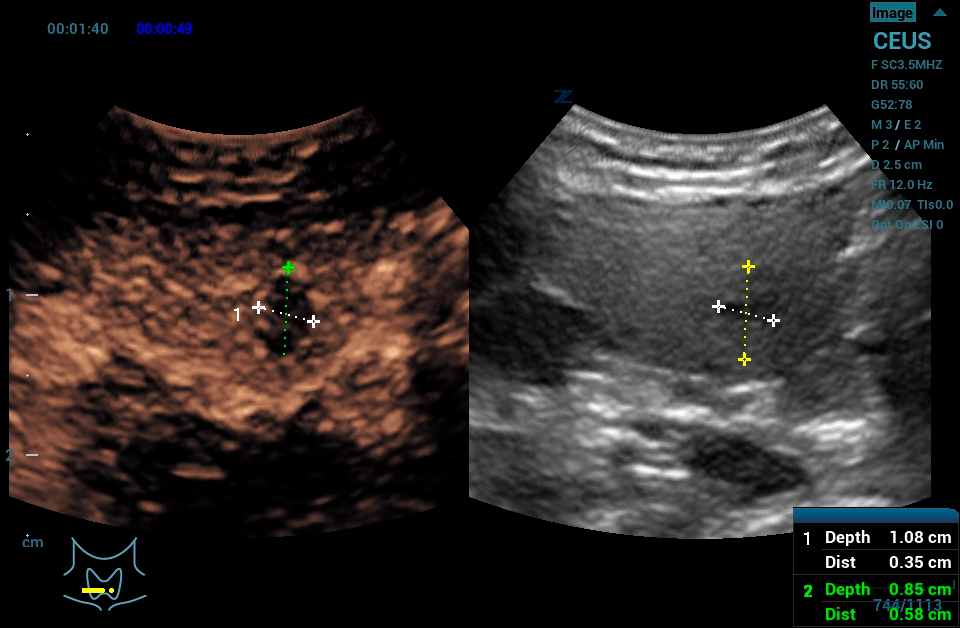

The Z.One PRO Ultrasound System Emerald Edition 2.0 is a powerful and portable advanced point-of-care imaging platform. Powered by software-based ZONE Sonography® Technology+ (ZST+), the Z.One PRO System provides optimal B-mode and Doppler imaging for patients, regardless of body habitus, helping ensure a reliable diagnosis. With a full family of transducers (from 2 – 20 MHz) and a wide range of applications, the Z.One PRO System is the imaging answer to your difficult clinical cases.